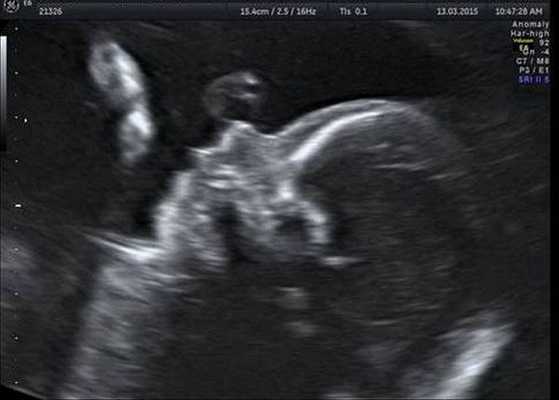

По данным ВОЗ, врождённые пороки развития становятся причиной практически каждого пятого случая. Выявление врожденных пороков в антенатальном периоде

Как правило, диагностировать синдром Гольденхара не составляет труда. Постановка этого диагноза основана на оценке внешних признаков, клинической симптоматике и результатах дополнительных исследований — КТ, рентгенографии, МСКТ черепа, эхокардиографии и ультразвуковой диагностики. КТ, как правило, проводится для подготовки ребёнка к оперативному лечению.

Индивидуальная профилактика синдрома предполагает проведение медико-генетического консультирования семьи и пренатальной ультразвуковой диагностики беременной женщины в установленные сроки [12] .

- Инструментальная визуализация. Чтобы подтвердить или исключить соматические пороки, при синдроме Гольденхара проводятся рентгенография грудной клетки, эхокардиография, УЗИ органов брюшной полости. Для исследования ЦНС применяется КТ или МРТ головного мозга.

Основу профилактики синдрома составляет антенатальная охрана плода. Критическим периодом является первый триместр, поскольку именно в это время возникают характерные костные аномалии. Беременным женщинам рекомендовано избегать контакта с химикатами, рентгеновским излучением, а также соблюдать противоэпидемические меры для защиты от вирусных инфекций.